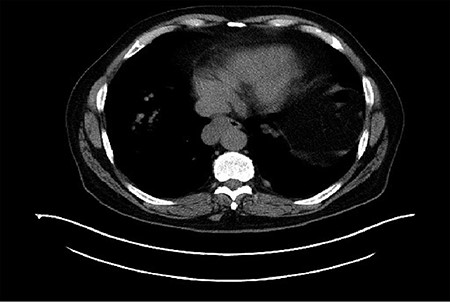

The patient is a 67-year-old male with a history of atrial fibrillation and hyperlipidemia who presented with several months of dysphagia to solids. The endoscopic evaluation revealed a ~4 × 2.3 cm submucosal lesion arising from the muscularis propria in the distal esophagus (Fig. 1). The lesion was 2 cm proximal to the GE junction and intermittently disappearing with peristaltic contractions. The lesion was biopsied and showed low-grade GIST with 1–3 mitoses per high power field and was CD 117 positive. Computerized tomography (CT) scan showed a right esophageal mass without evidence of local invasion (Fig. 2).

Esophagogastroduodenoscopy showed an esophageal prominence 2 cm above the GE junction with endoscopic ultrasound confirming 39.8 × 23.2 mm mass.